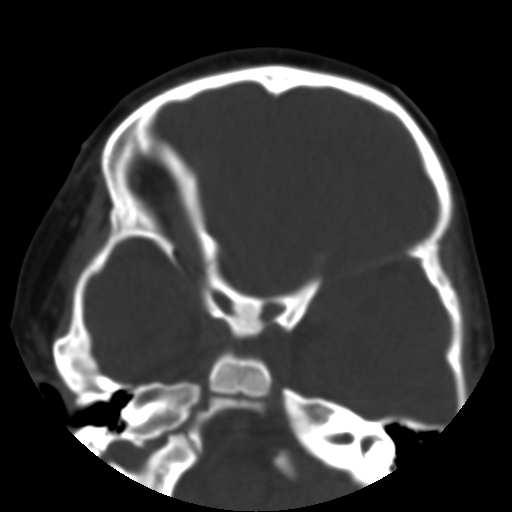

以下是引用深泽交通医院在2009-10-16 8:25:00的发言:[br]右眼环出血伴异物

以下是引用卜一在2009-10-16 15:01:00的发言:[br]右眼球挫裂伤伴异物!

以下是引用拾荒者在2009-10-17 18:38:00的发言:[br]鼻面部皮下积气,右侧睑缘及眼球壁高密度异物影,左侧眼球壁晶状体内侧缘处是圆形低密度影。低密度异物?应提请眼科医生注意。